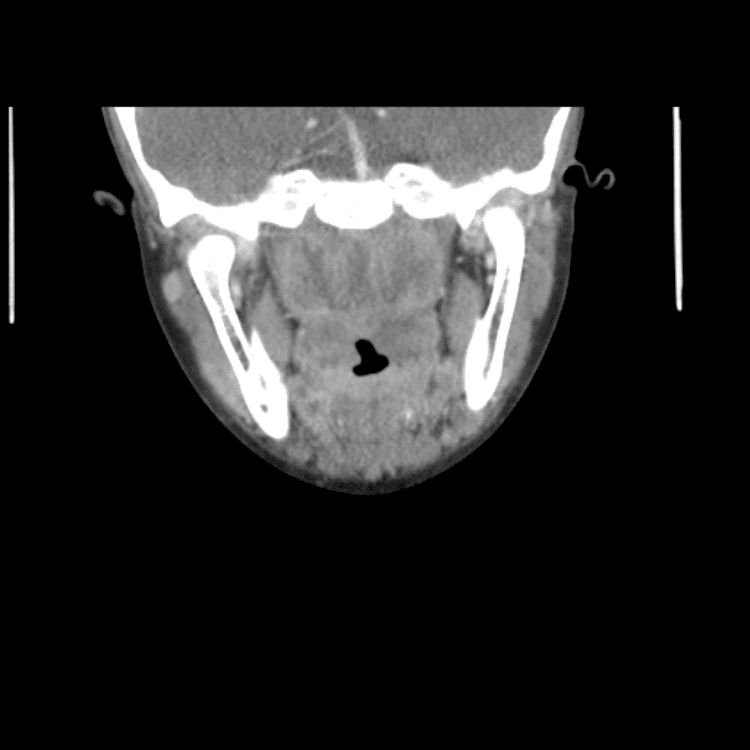

Head and Neck

Simulates call by including subtle or difficult cases and some normals.

27 cases